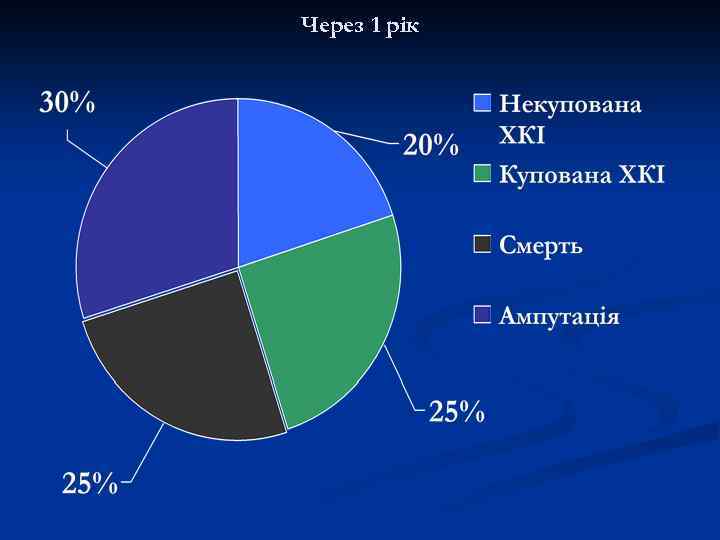

Через 1 рік

Через 1 рік